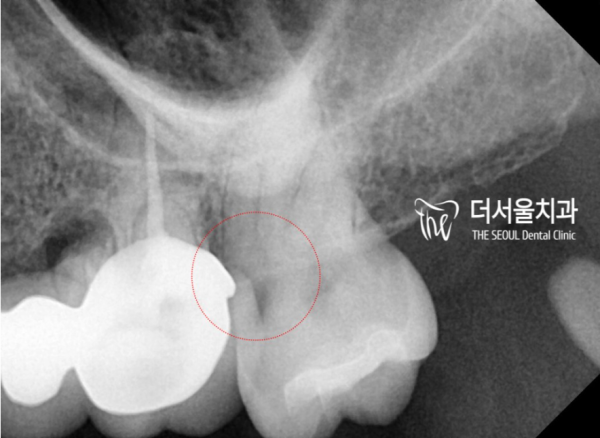

방사선사진에서는 충치의 위치가 확인됩니다.

신경과 상당히 근접한 부분까지 충치가 있기때문에

신경치료를 통해 치료를 하는것으로 판단하였습니다.

The radiograph confirms the location of the cavity.

There's a cavity in the area that's close to the nerve

It was judged to be treated through neurotherapy.